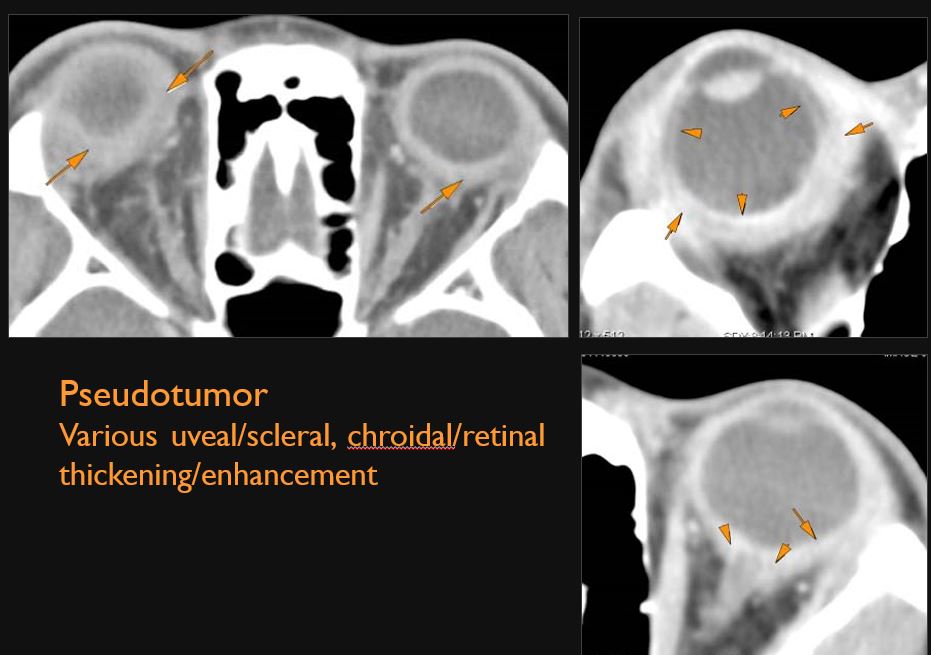

The uveal and scleral components of the globe are swollen or enhancing abnormally.

There is a hemorrhage or other abnormality causing a detachment of the choroid, hyaloid membrane and/or retina.